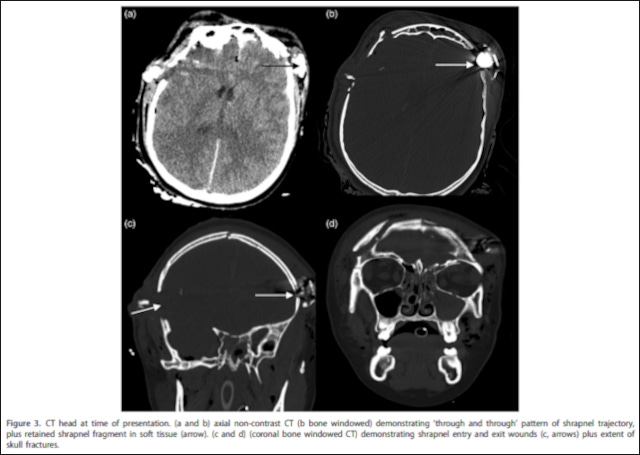

A 15-year-old was triaged as and received basic resuscitation at the scene, arriving at our institution at 00:25. [. . .] CT [computed tomography scan] brain identified a ‘through and through’ pattern of injury from a shrapnel trajectory, extensive scalp fractures and evidence of retained shrapnel fragment. [. . .] A piece of shrapnel in the form of a large metal nut was retrieved from left fronto-temporal soft tissue.

While Eve was 14 at the time, it is stated in the paper that identification of patients was difficult. Images were produced to show the extent of the damage reportedly sustained by Eve.

Reporting that the patient was discharged following 9 months in hospital, the paper outlined the patient’s recovery status less than a year after reportedly sustaining the injury shown above:

They have a left upper limb spastic mono-paresis but are independently ambulant, fully conversant, attending school and are receiving ongoing psychological support.

This appears to be extraordinary evidence substantiating an extraordinary claim. The paper was first published in July 2020, more than three years after the injury was supposedly incurred. The paper corresponds precisely to the official narrative that was outlined in the Saunders Inquiry that convened less than two months after the paper was published. It is another example of the detailed secondary evidence presented to substantiate the official account that Brent and Neil have found so convincing.